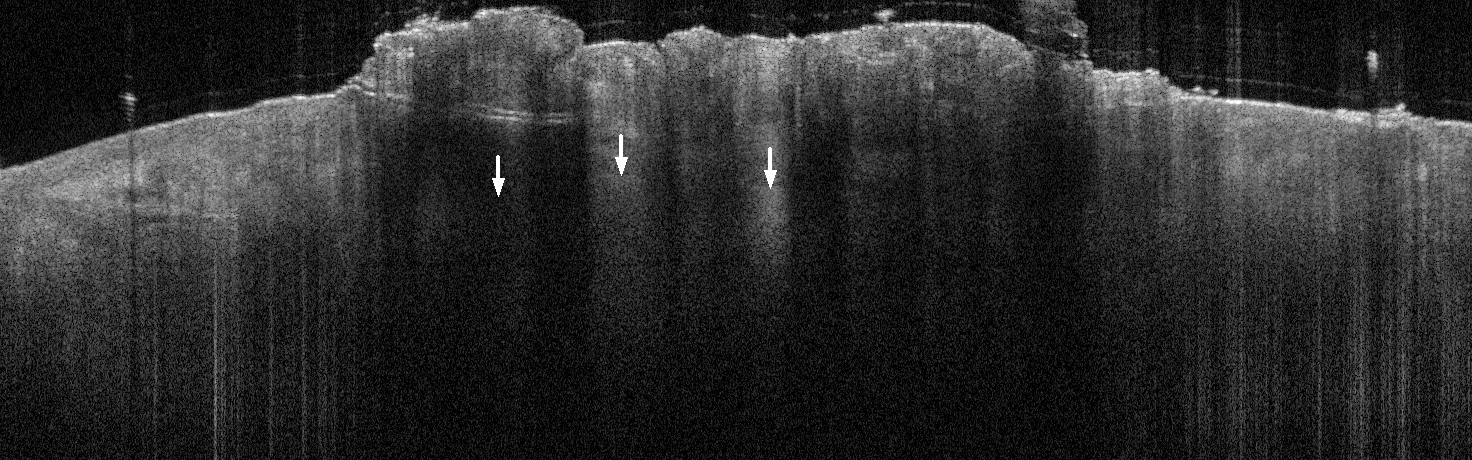

VA38: Upper Forehead, Left of Midline, Actinic Keratosis, Hypertrophic

- Arrows indicate base of epidermal thickening